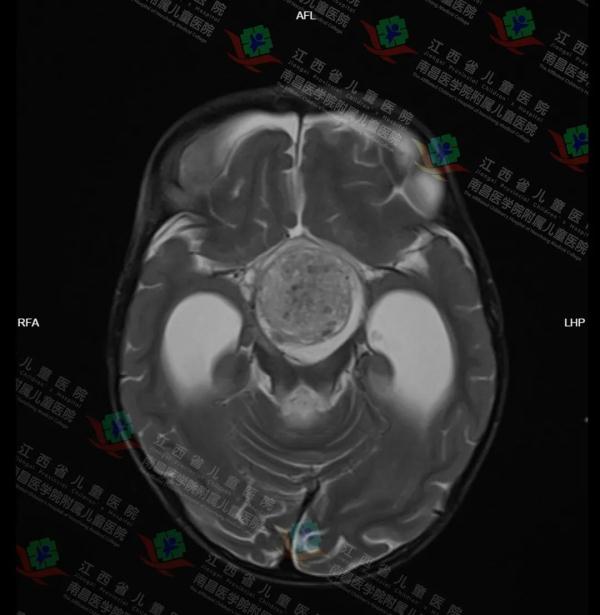

在入院完善相关检查后,颅脑CT显示,鞍区(颅底)占位并脑积水,立即为其办理入院并完善颅脑磁共振等相关检查,可见肿块大小约为37mm×35mm×55mm,神经外科主任医师杨明团队考虑女童有颅咽管瘤可能,根据女童的情况展开多次讨论,考虑到肿瘤大且位置深,周围毗邻下丘脑、垂体、视交叉、颈内动脉等重要脑功能区域,病情危重,决定为其尽快实施颅内肿瘤切除术并制定详细手术方案。